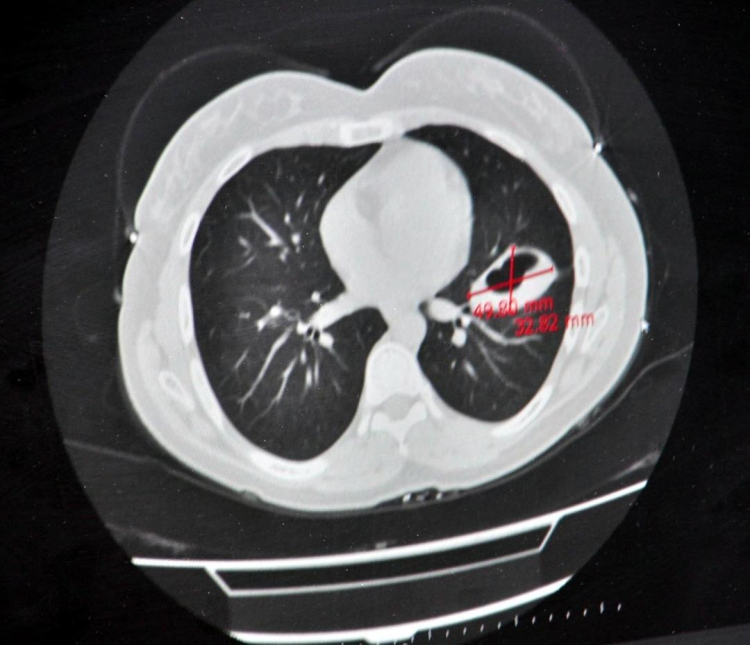

Hastalığın başlarda kistin küçük olduğu dönemlerde uzun yıllar boyunca belirtisiz seyredebileceğini söyleyen Perincek, “Fakat kist büyüdükçe, bulunduğu bölgeye ve oluşturduğu basıya göre belirtiler ortaya çıkar. Kistler en sık karaciğer ve akciğerlerde görülürler. Nadiren dalak, karın zarı (periton), böbrek, kemik, göz yuvası, beyin, kalp ve yumurtalıklara da yerleşebilir. Karaciğer yerleşiminde karnın sağ üst kısmında ağrı, bulantı, kusma ve bazen kaşıntı, sarılık gibi belirti görülür. Akciğer tutulumunda solunum sıkıntısı, öksürük, ağızdan kan gelmesi ve göğüs ağrısı olabilir. Diğer organ ve sistem tutulumlarında da bu bölgelere ait tablolar ortaya çıkar. Örneğin kafa içi tutulumlarda; baş ağrısı, kusma, şuur kayıpları görülebilir. Kalp tutulumunda kalp ritim bozuklukları, enfarktüs bulguları, hatta kalp duvarında yırtılma olabilir. Kemik tutulumlarında kırıklar olabilir. Kist patladığında alerjik reaksiyonlar ortaya çıkabilir” diye konuştu.